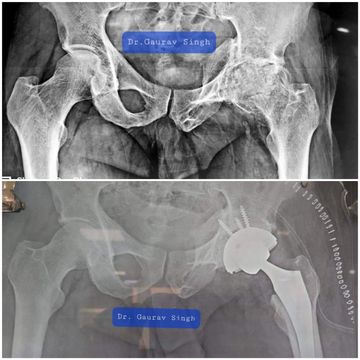

Degenerated and Severely Damaged joint replaced with uncemented total hip replacement

Uncemented femoral stem and head placement

The hip joint is one of the body's largest weight-bearing joints, located between the thighbone (femur) and the pelvis (acetabulum). It is a ball and socket joint in which the head of the femur is the ball and the pelvic acetabulum forms the socket. The joint surface is covered by a smooth articular cartilage which acts as a cushion and enables smooth movements of the joint. When the cartilage is worn away due to arthritis (either due to injury, degeneration, inflammatory process), there is pain, stiffness and restricted movement of the hip.

Total hip replacement is a surgical procedure in which the damaged cartilage and bone is removed from the hip joint and replaced with artificial components.

This allows the hip to be pain free and move smoothly aiming to establish healthy hip function & provide you with a superior quality of life.

i will make an incision on the side of your hip and expose and dislocate your hip joint. Using specialized instrumentation and jigs, the damaged/degenerated portion of the hip is cut, sized and shaped to fit the components of the hip replacement. The hip joint is balanced and trialed to ensure stability and correct alignment. The hip implants are then fitted with or with out the use of special bone cement. The cup is made of metal which sits in the acetabular socket, the stem is made of metal inserted into the femur. The bearing surfaces which include the femoral head (metal or ceramic) and liner (plastic or ceramic), articulate with each other.